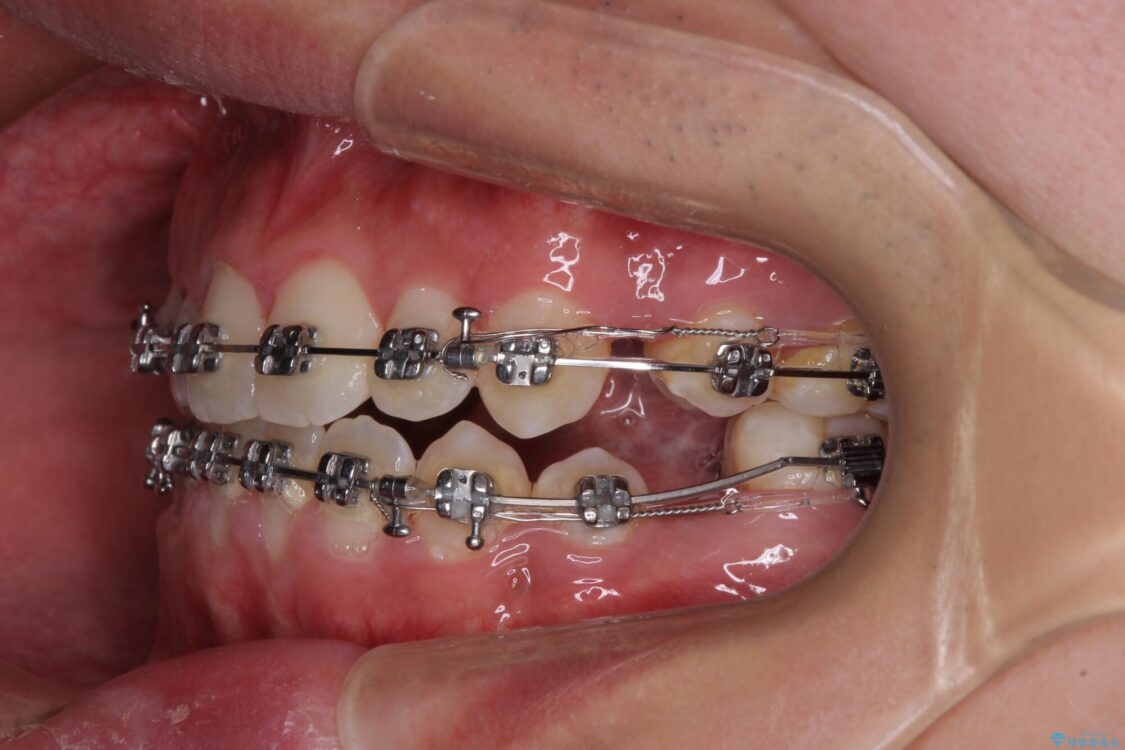

治療途中

• 口元の突出感を改善 受け口傾向の咬み合わせの抜歯矯正 治療途中画像